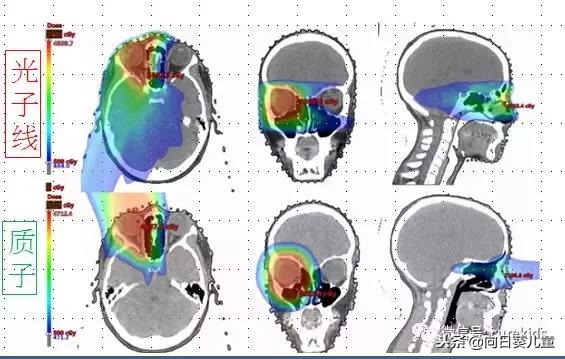

这是髓母细胞瘤,左侧是3-照野质子治疗,右侧是光子线治疗。针对瘤床做补强时,3-照野质子治疗是在整个后脑小脑部的左侧,整个剂量就停下来了;如果使用光子线治疗,整个左侧都被一些中、低剂量的光子射线照射到。

这是左眼的眼眶横纹肌肉瘤的治疗案例。如果用光子射线治疗,就会穿透到右边的脑部区域,使用质子线治疗时,它会停下来,所以就不会影响到中间的脑垂体和另外一边的脑部区域。

从以上例子可以看出,对于偏一边的肿瘤,光子线跟质子线两种在整个治疗经过的路径上会有明显的差异。